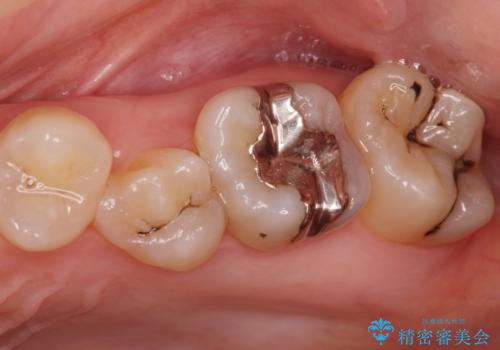

[ 歯肉縁下齲蝕 ] 歯周外科を行った虫歯治療

黒くなった奥歯をジルコニアクラウンに